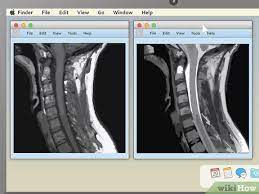

How To View Mri Cd On Dvd Player : Mine also works only on 32 bit.. If the data is formatted as a television signal and then stored on a dvd, it is quite possible that the images can be. Double click on the "viewer" folder. How to watch a doctor's xray on a cd? Speak with the imaging department and ask them to describe the format of the cd and ask them for instruction on how to view it, what viewer to use and where such viewer can be found. Nov 05, 2012 · if mri data is stored on tape, then it can't be played on any disc player.

See full list on wikihow.com See full list on wikihow.com If the data is formatted as a television signal and then stored on a dvd, it is quite possible that the images can be. The images are stored in the dicom folder shown above. I got to the written diagnosis by opening the e: May 09, 2014 · look for a file named dicomdir on the cd; Am somewhat savvy as to spine pics and would like to view these. Mine also works only on 32 bit.

This will launch inteleviewer which will show your images. See full list on wikihow.com How can i see the mri images on my computer? Whether you need to extract the images so you view them on a phone or tablet, or whether you want to extract the images so you can add them to trial director. Today, i received a cd copy of my mri from my radiologist. Double click on the "viewer" folder. Mine also works only on 32 bit. Speak with the imaging department and ask them to describe the format of the cd and ask them for instruction on how to view it, what viewer to use and where such viewer can be found. Am somewhat savvy as to spine pics and would like to view these. Is designed to display most medical images: The images are stored in the dicom folder shown above. More than a dicom viewer, athena dicom essential marks a new generation of software to view and manipulate medical images. Folder but no medium i have will open the pics.